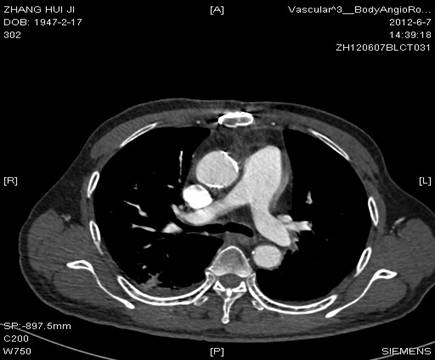

图1:CT扫描示升主动脉钙化